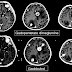

Diagnosis

Brain imaging (neuroimaging such as CT or MRI) is needed to determine the presence of brain metastases. In particular, contrast-enhanced MRI is the best method of diagnosing brain metastases, though detection is primarily done by CT. Biopsy is often recommended to confirm diagnosis.